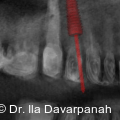

Die moderne Implantologie vereint heute funktionelle Stabilität mit höchsten ästhetischen Ansprüchen. Gerade im Frontzahnbereich hängt der Behandlungserfolg entscheidend von der präzisen Planung, der gewebeschonenden chirurgischen Umsetzung und einer frühzeitigen prothetischen Integration ab. Fotos: © Dr. Ila Davarpanah